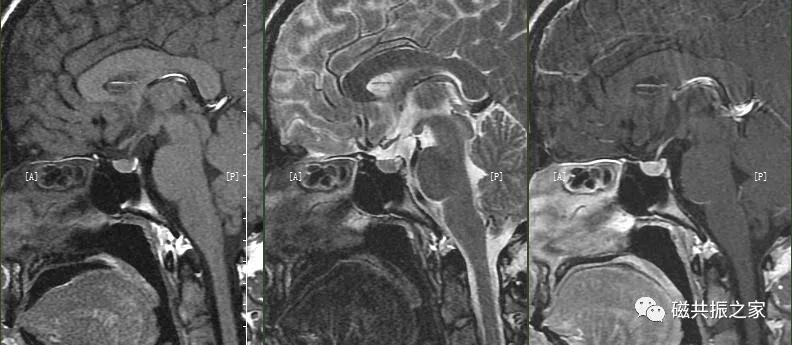

矢状位:SAG T1 FSE 矢状位T1加权序列

以冠状位和横断位作为参考定位。在横轴位上与大脑矢状裂平行;在冠状位上定位线与垂体柄平行,双侧对称扫描。FOV中心置于垂体位置,扫描范围包括整个垂体,根据病变大小调整范围,需包括整个病变范围。

矢状位是显示垂体前后叶最理想的方位。

FOV不宜过大,14~18cm。

使用NPW(去卷折伪影)技术,相位编码方向为前后。

添加上下、前后饱和带可减轻脑脊液,血管搏动伪影。

在不同的年龄阶段,垂体的MRI 信号有所不同,新生儿整个垂体在T1WI 上表现为高信号,约6周以后,垂体前叶的信号强度逐渐减弱并最终与脑皮质相似,而垂体后叶组织内具有较多的神经分泌囊泡则表现为高信号,若高信号缺失则可能与中枢性尿崩症或垂体腺瘤受压有关。

腺垂体可以分泌多种激素,其在T1WI上呈相对低信号,与脑皮质信号相仿;神经垂体虽然不分泌激素,但其可储存下丘脑分泌的激素,在T1WI上常表现为高信号。

矢状位:SAG T2 FSE 矢状位T2加权序列

复制SAG T1 FSE定位线。

使用NPW技术,相位编码方向为前后。

在常规序列中,T2WI序列在一定程度上可以评价垂体瘤质地的软硬度。

肿瘤质地的评估可以为手术方案的制定提供一定的参考依据。虽然T2WI序列在一定程度上可以对垂体瘤质地进行评估,但建议使用更有优势的序列,如动态增强序列、自由稳态序列、MRE等进行评估。